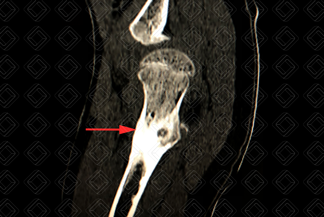

Texto alternativo para a imagem Figuras 1 e 2. Créditos: Dra. Elazir Mota - Rio de Janeiro/RJ

Descrição das figuras 1 e 2: Tomografia computadorizada do quadril direito evidenciando lesão com nidus central (setas vermelhas) na cortical da região metadiafisária do fêmur direito, compatível com osteoma osteoide.

• Tomografia computadorizada: Boa para localizar com precisão o nidus e determinar seu tamanho. Pode ser útil no planejamento de radiologia intervencionista (figuras acima);